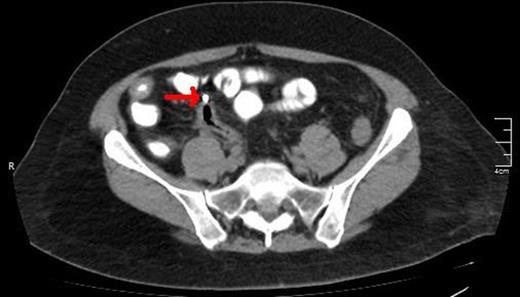

A lower CT view of the same patient showing the stent (red arrow).